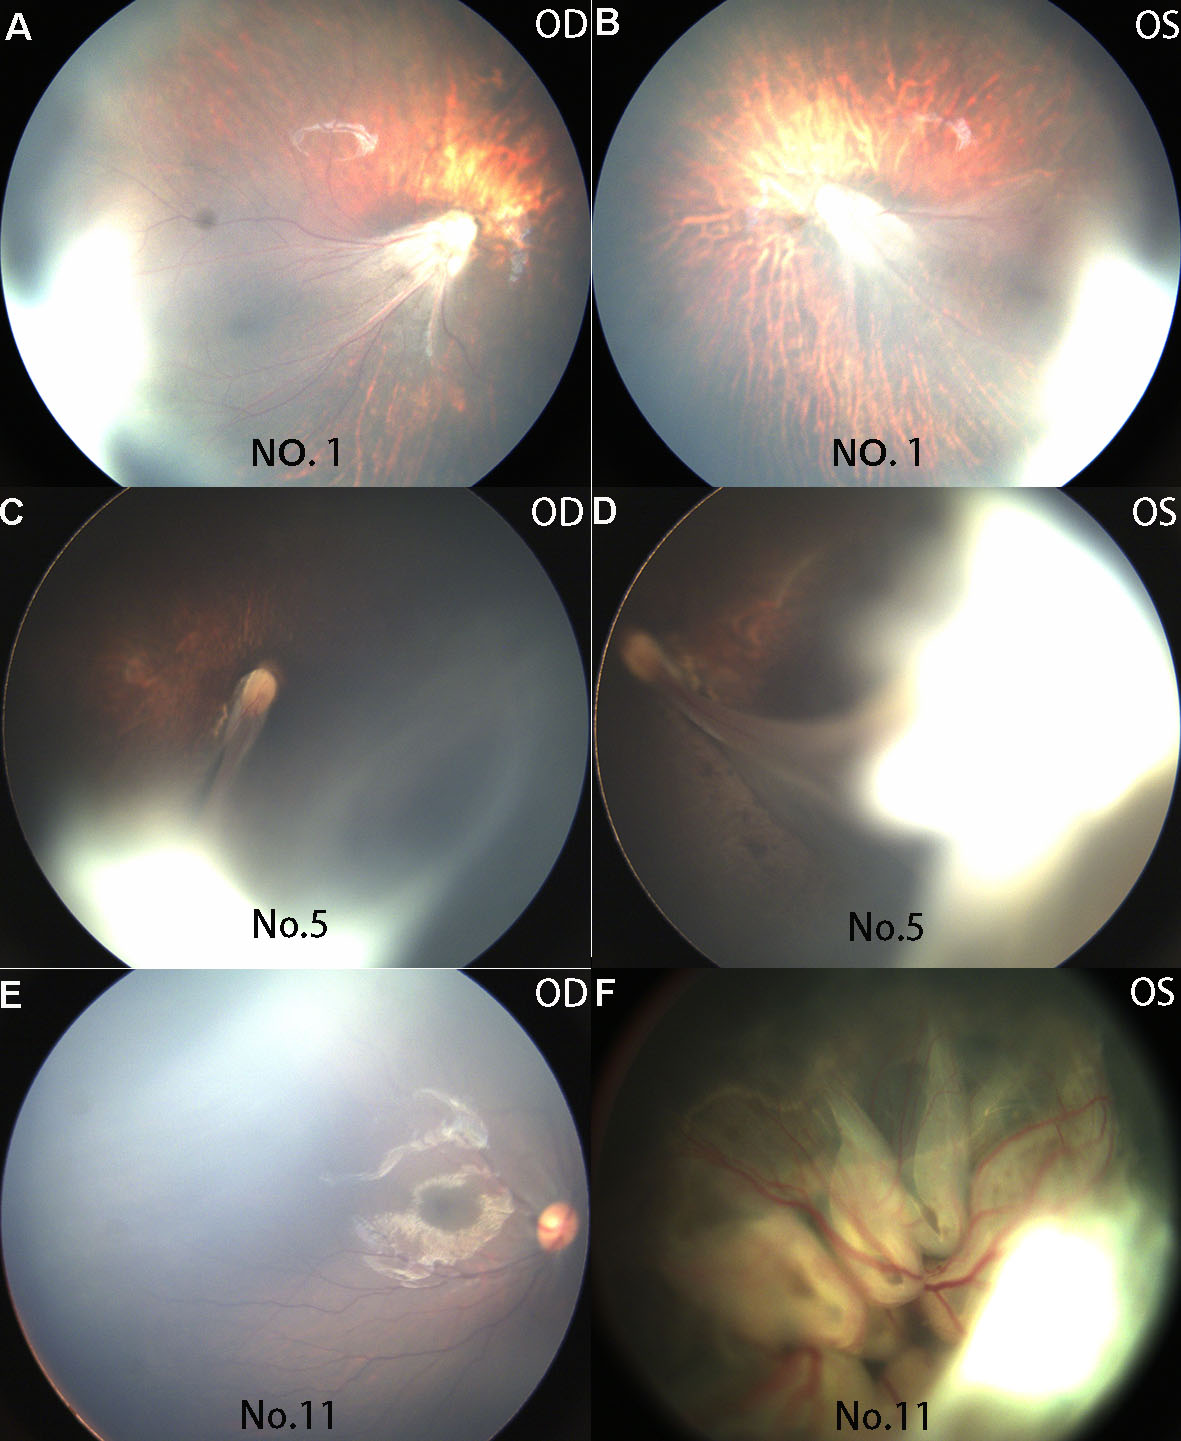

Figure 2. Representative fundus presentations of patients with the KIF11 mutation c.2153A>T (p. H718L). Ocular phenotypes included temporal disc dragging (A, B), knife-like retinal fold (C, D), aberrant peripheral retinal vessels (E), and total retinal detachment (F). The patient number is marked at the bottom of each fundus photo. OD and OS represent the right and the left eye, respectively.